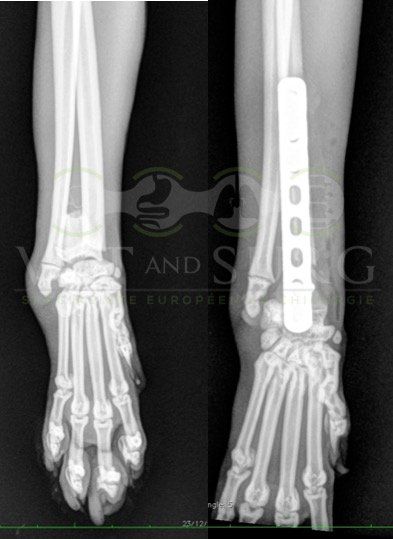

Fracture Salter-Harris sur un chaton Européen de 10 mois

Spike, chaton européen mâle de 10 mois, a été présenté en consultation pour boiterie du membre postérieur droit à la suite d'une chute depuis le 1er étage.

A la radiographie, une fracture de type Salter-harris 1 est diagnostiquée, avec déplacement de l'about discal.

Une réduction de la fracture par pose de 2 broches en croix a été réalisée.